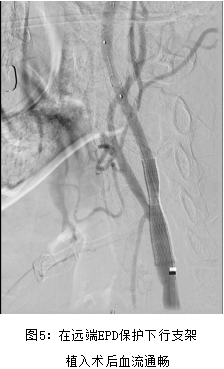

王先生,77岁,2月前无明显诱因出现头晕、黑矇、双下肢乏力,步行20余米需停下休息,1月前曾因下肢无力在家中摔倒1次,后于骑电动车途中摔倒1次。曾于外院输“活血”药物治疗,无明显好转。就诊于我院普内科,完善详细检查后考虑左侧颈动脉狭窄、脑梗。王老先生既往慢性疾病较多,15年前发现肺气肿、肺大疱及慢性支气管炎等慢性阻塞性肺病;2011年因急性心梗于行PCI术治疗,植入2枚支架,近期偶有心绞痛发作;同时还有高血压、慢性肾功能不全等疾病。术前超声造影提示:左侧颈动脉重度狭窄,局部峰值流速约200cm/s,斑块可见较多造影剂微气泡及细线样灌注;考虑为不稳定斑块。因患者心肺肾等重要脏器功能欠佳,无法耐受颈动脉内膜剥脱手术,经多学科MDT讨论评估后决定行微创颈动脉支架治疗;赵克强副主任医师在局麻下为王先生进行了微创颈动脉支架手术,40分钟内手术顺利结束,仅仅用了不到50ml造影剂,避免肾功能的进一步恶化,术后3天康复出院。术后随访期间老王未再次出现头晕、黑矇等TIA发作表现。